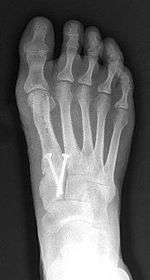

Syndesmosis procedure addresses specifically the two fundamental problems of metatarsus primus varus deformity that gives rise to the bunion deformity. They are leaning and instability of the first metatarsal bone . Syndesmosis procedure uprights the leaning first metatarsal bone with strong binding sutures between it and the second metatarsal bone (Fig. 2) and then also stabilizes it uniquely by creating a fibrous connecting bridge between these two bones (Fig. 3,4). First metatarsal bone can be readily realigned is because by definition of the metatarsus primus varus deformity its first metatarsal is abnormally loose and mobile.

- Second metatarsal stress fracture (Fig. 5)

- Over-correction (Fig. 6)